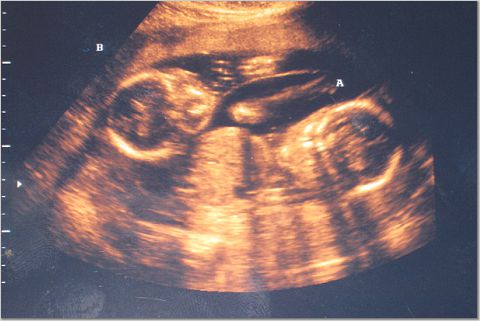

I just wanted to write a quick note and let everyone know that we went for our 20 week (5 month) sonogram this morning.

Most importantly, everything is moving along very nicely. Both twins are growing on schedule, all the organs are in place, and there are no signs of any problems.

I am proud to announce that Christine and I are the proud parents of two baby GIRLS!!!

I have attached a few sonogram photos. The third picture is our favorite, as you can see both heads in the same shot.

MEGHAN MARIE aka Baby "A"

DEBORAH ROSE aka Baby "B"